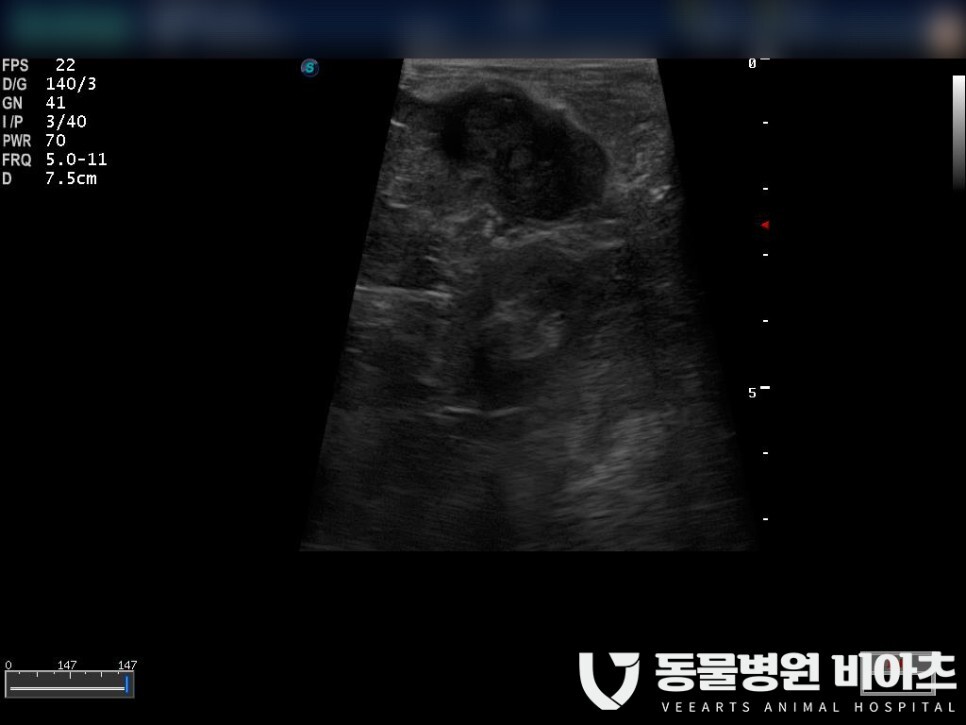

검사 결과는 초음파상 보이는 것처럼

안타깝게

종양이 발견되었습니다.

비장의 이상 여부를 확인할 수 있는

가장 좋은 검사 방법은 복부 초음파 검사입니다.

실질의 질감(texture)이나 모양을 확인할 수 있습니다.